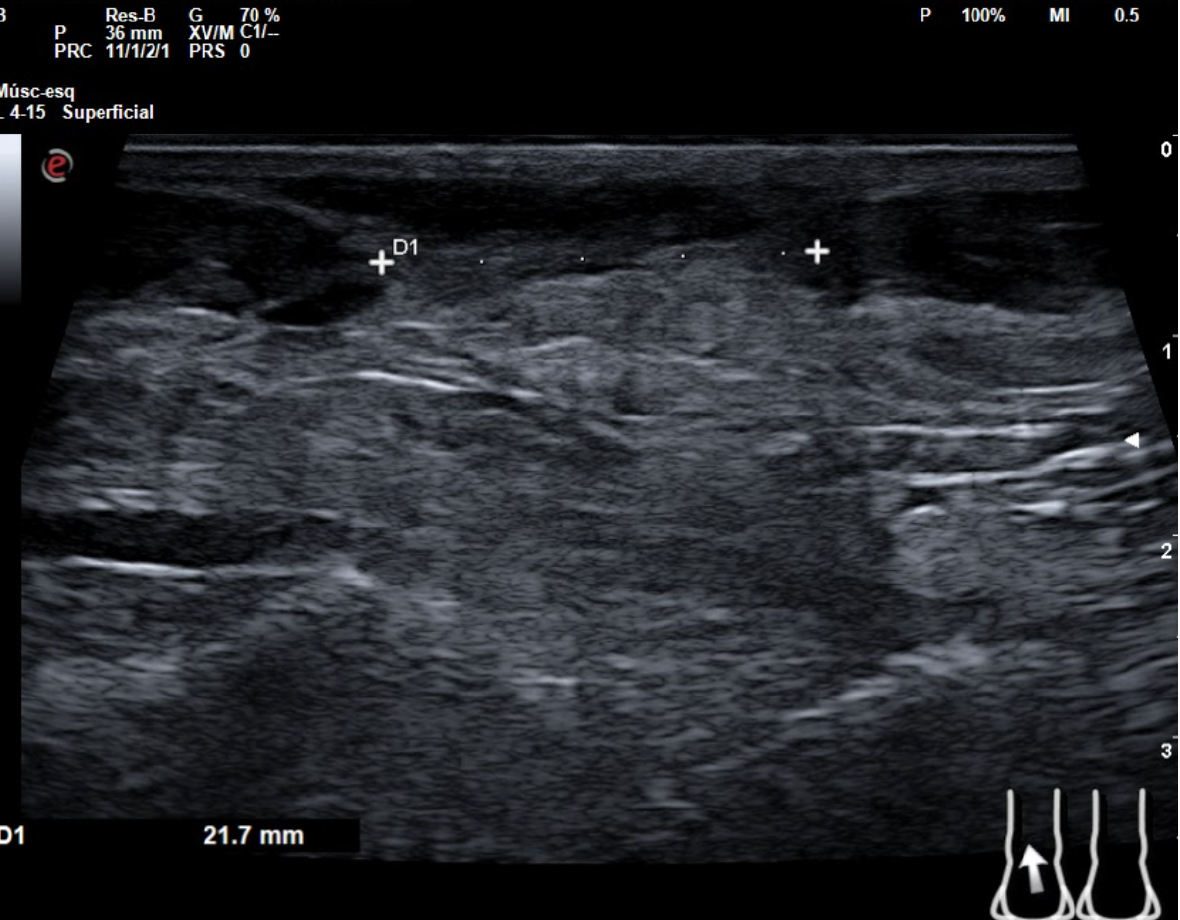

En tendón aquíleo izquierdo se aprecia rotura completa con solución de continuidad de 2 cm localizada a 5,7 cm de su inserción en el calcáneo. Presenta áreas hipoecoicas peritendón que sugieren hematoma secundario. En el aquíleo derecho presenta leve hipoecogenicidad y engrosamiento del tendón sin solución de continuidad que sugiere tendinosis. Importante componente inflamatorio. No datos de TVP. Poplítea y safena externa permeables y compresibles en ambas extremiedades.

Juicio clínico: Rotura completa de tendón de Aquiles izquierdo. Tendinosis aquílea derecha.